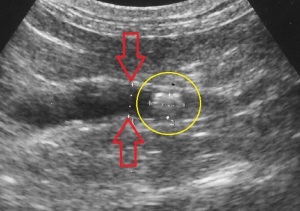

レントゲン検査により腎臓や尿管に結石が見つかった場合、さらに超音波検査によって結石の正確な位置関係とそれが周囲に及ぼす影響を評価します。下の2枚の写真は超音波検査の画像です。尿は左から右写真方向に「黒い管」として見える腎盂~尿管の中を流れます。

右下写真の黄色い円の中に見える「白いカタマリ」が尿管結石で、おおよそ3ミリくらいの直径があり、尿管を閉塞しています。

腎臓でつくられた尿がつまっているために尿管は重度に拡張しており、結石のすぐ上流で直径が4mm(赤矢印)、さらに腎臓の出口付近では1cm以上(緑矢印)にもなっており、腎臓内が拡張した水腎症になってしまっています。

通常では猫の尿管は極めて細いため超音波検査ではほぼ見ることができませんので閉塞の程度をイメージできるのではと思います。